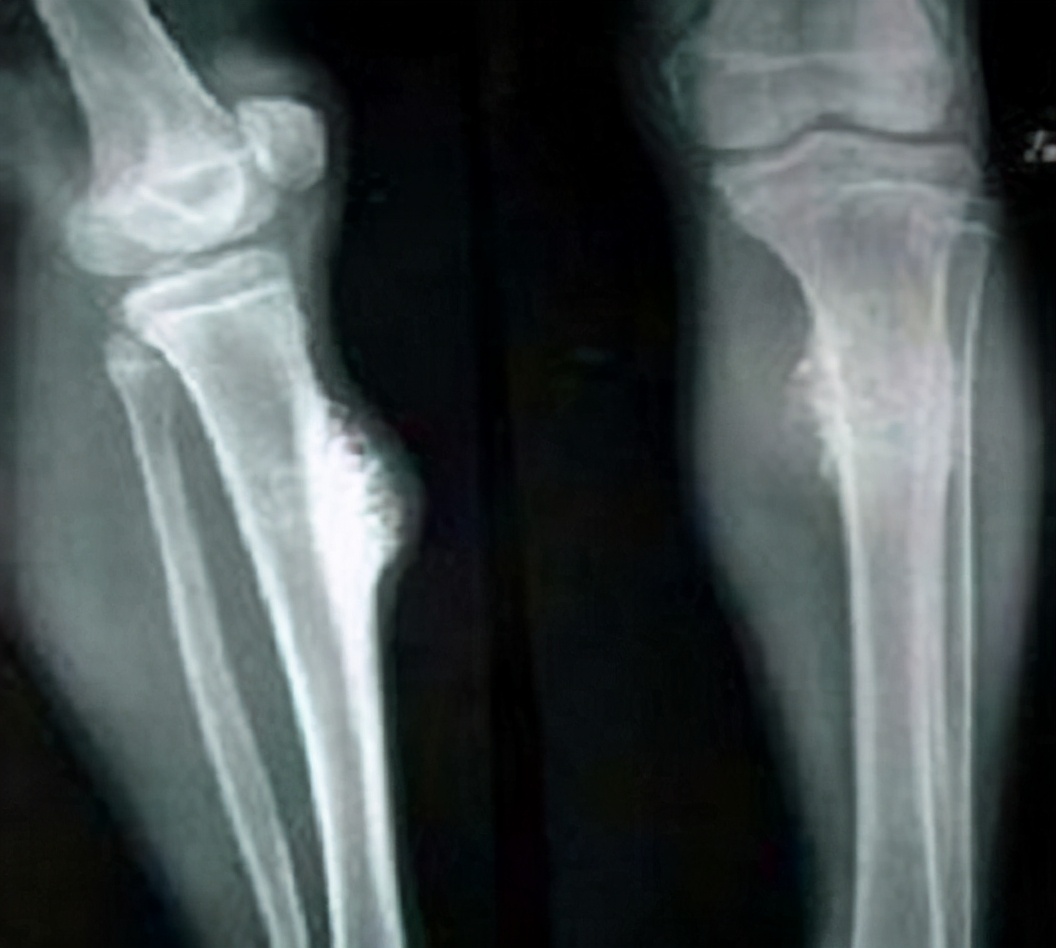

如果患者的评分情况是临近骨折,在x光片看到骨的溶解破坏了三分之一,这个时候就要及时处理了!就好像一栋楼的一侧支柱已经烂掉了很多,这个楼就随时会有倒塌的风险,这时就需要及时处理、加固了。

虽然疼痛虽是骨转移的特征,但最好还是要定期复查,因为疼痛并不意味着就是转移了,还需要结合其他方面的检查,才能确定,比如X线检查、CT检查、PET—CT检查、MRI检查及全身骨扫描(ECT)等。